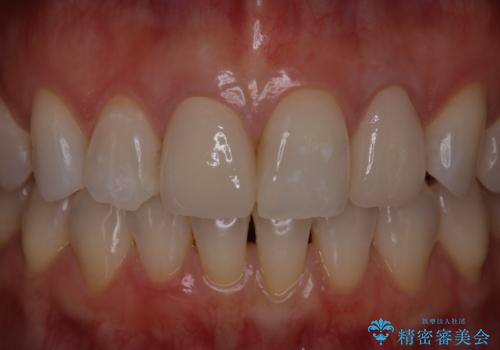

歯茎の出来もながなくなり、患者様にセラミックの色も満足いただけました。